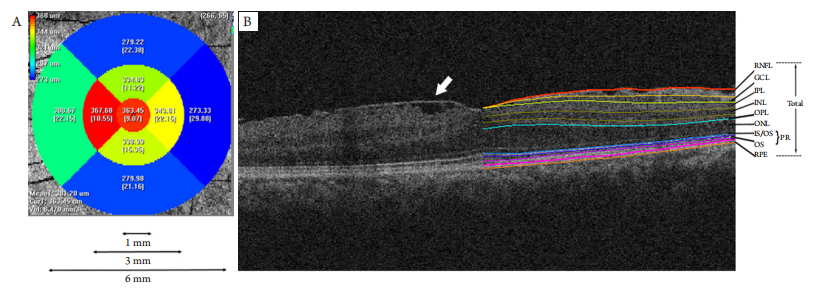

所有患者进行BCVA、裂隙灯、+90D前置镜(散瞳后)、OCT等检查。以黄斑中心凹为中心,应用Macular Cube 512×128模式对所有前膜眼进行扫描,以获取6 mm ×6 mm范围内黄斑区视网膜数据。将所获取的OCT源文件运用Iowa Reference Algorithm (Version 3.8)进行读取及运算,从而获取视网膜各层在直径分别为1、3、6 mm的3个同心圆,共9个亚分区(1个圆形区域,8个扇形区域)内的平均厚度值(图1)。

图1 分区及视网膜分层示意图

(A) Iowa Reference Algorithm将OCT采集的区域自动分成9个亚分区并测量每个分区的平均厚度值。这9个分区同时构成了3个直径分别为1、3、6 mm的同心圆区域。(B)1例前膜患者黄斑区OCT图像及视网膜分层示意图。左半部分可以看到视网膜表面的前膜组织(白色箭头)。右半部分为同一只眼经软件自动分层后的各视网膜层次。IS/OS:光感受器的内节/外节交界处;OS:外节;RPE:色素细胞层。